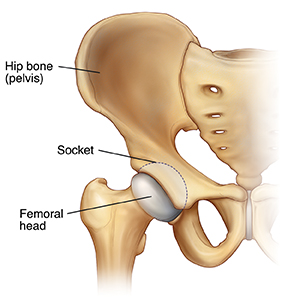

Developmental hip dysplasia happens when the rounded top of the leg bone (the femoral head) slips partly or completely out of the hip socket. The hip socket may be too small or too shallow. This problem is more common in female children, in firstborn children, and in children born into families with a history of this condition. It is also more common in babies who are positioned feet first (breech) in the uterus.